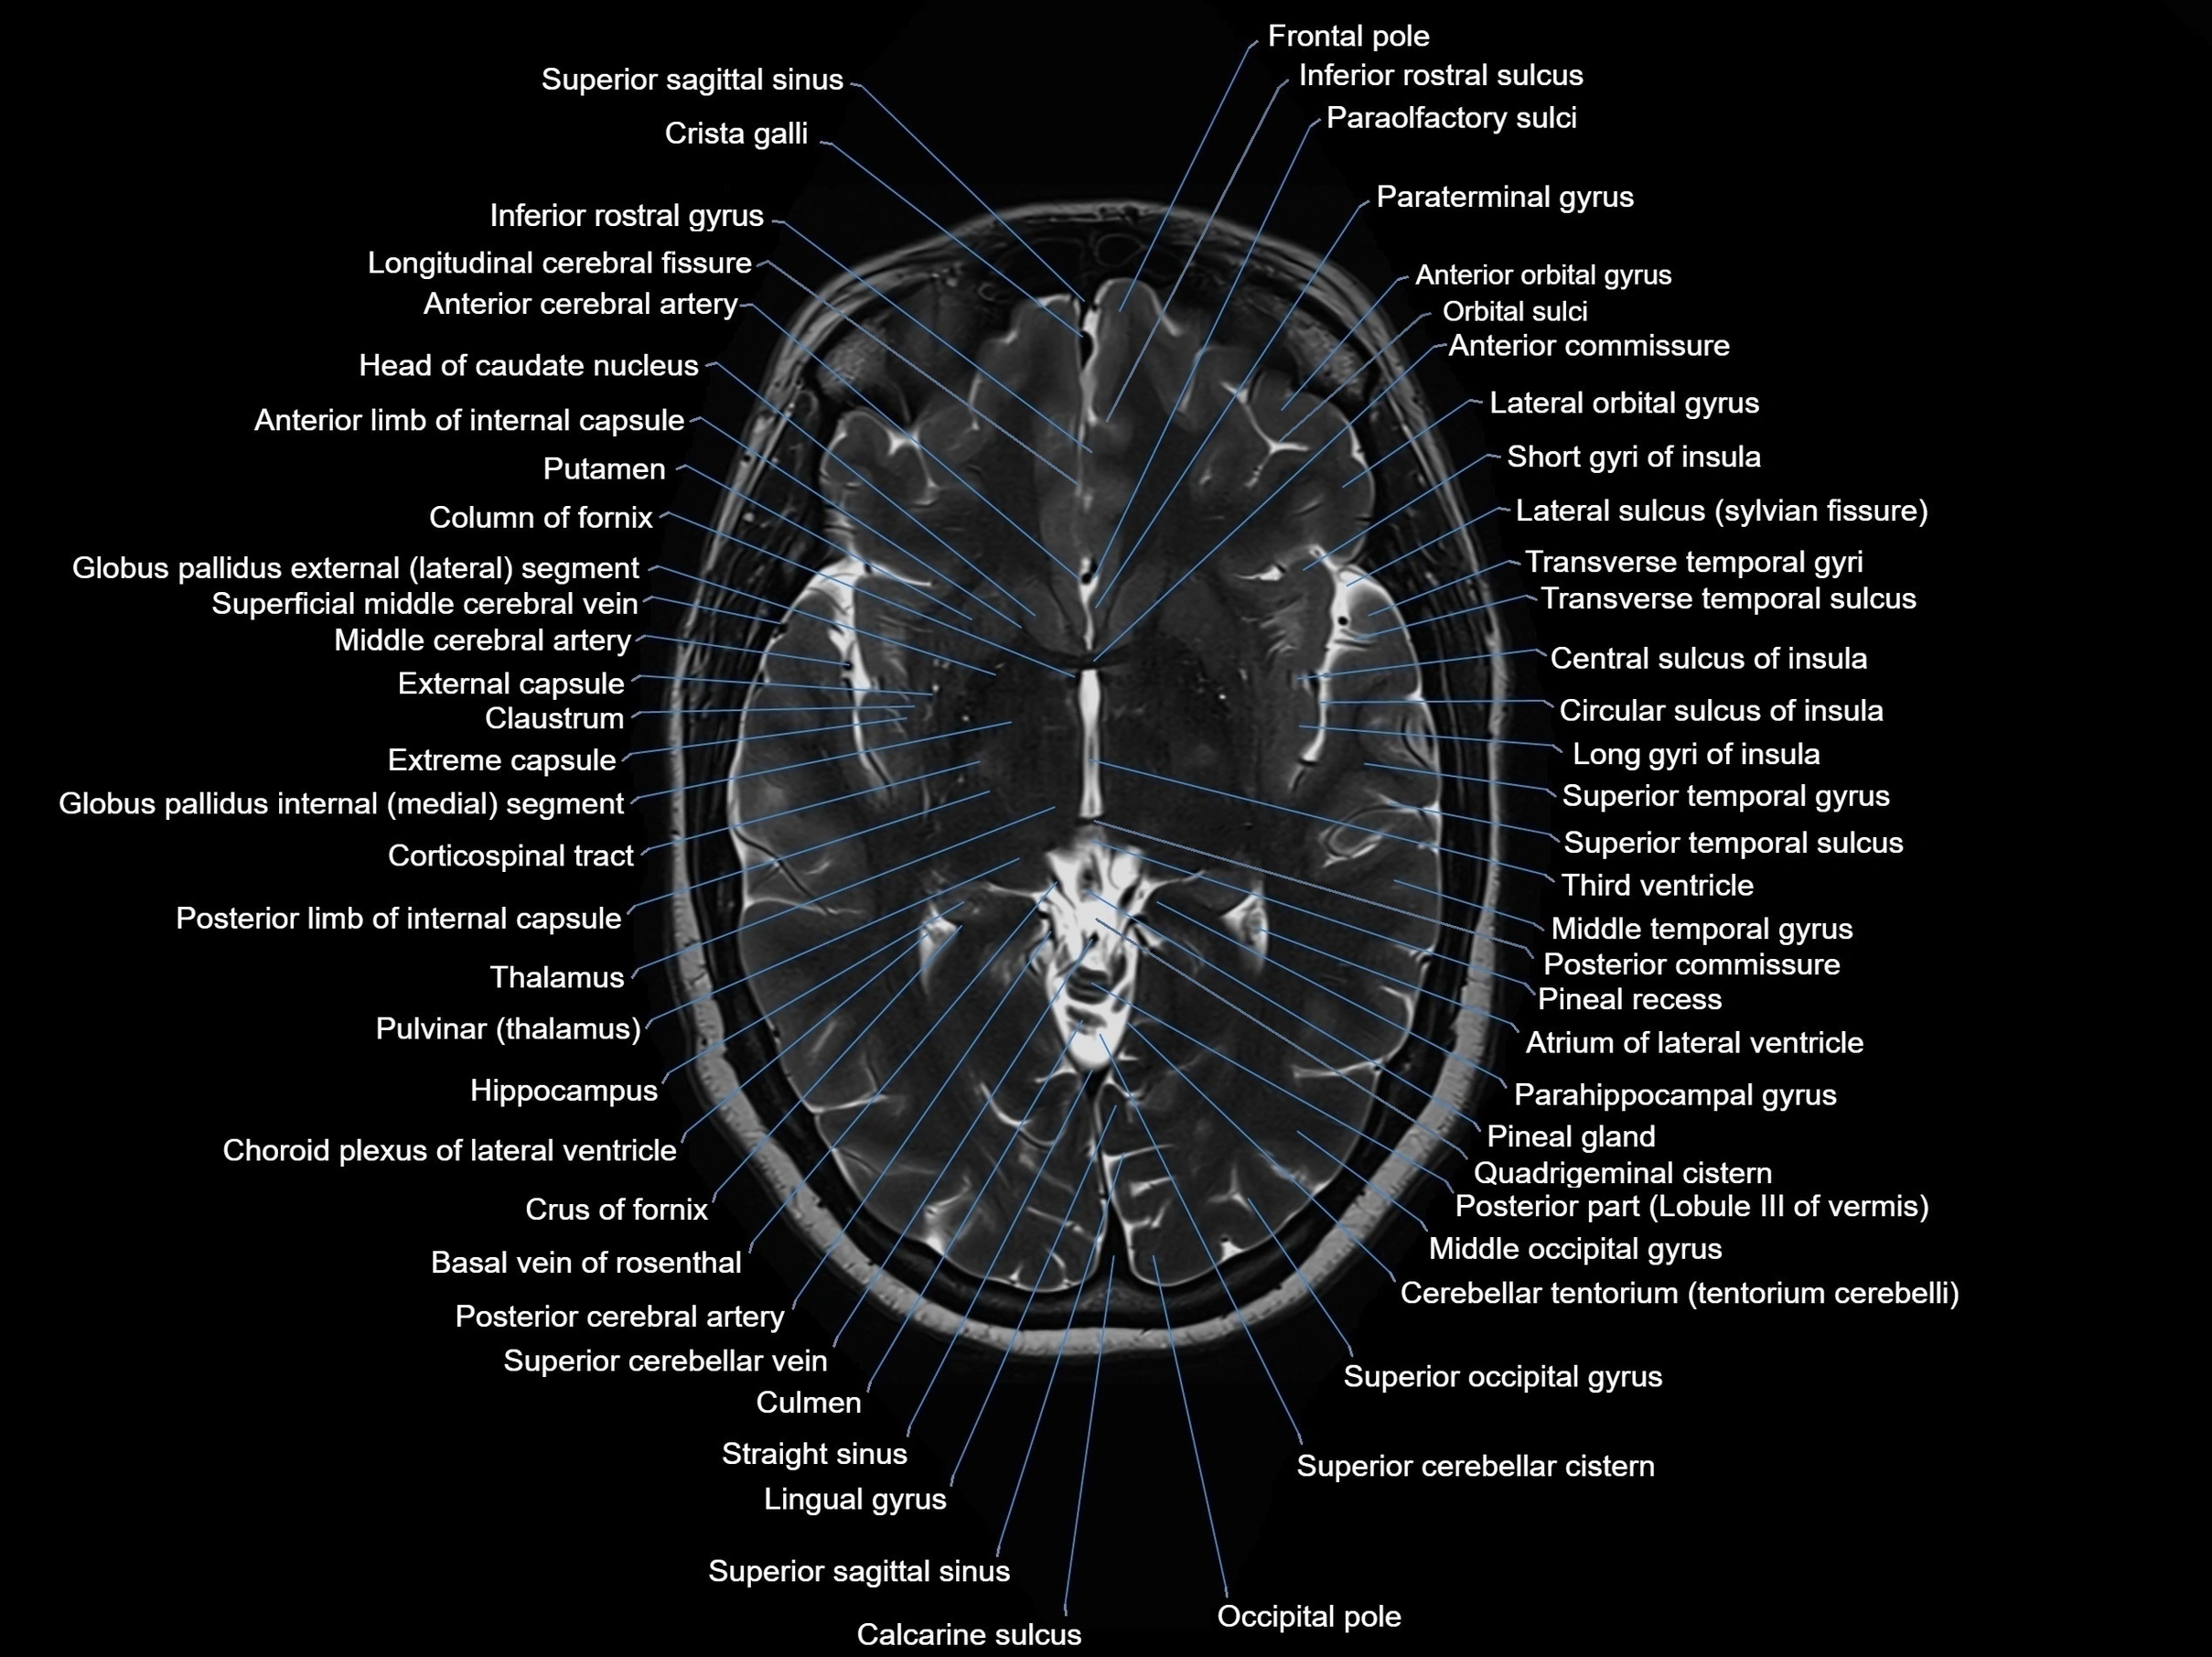

MRI images